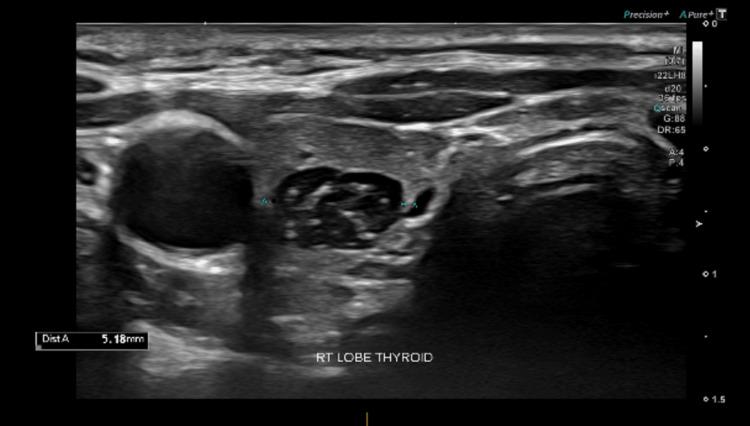

We present a case of conservatively managed intrathyroidal thymic tissue in a 3.5-year-old girl, who had an ultrasound for a midline swelling that was consistent with a dermoid cyst, proven by operative specimen pathology. An incidental finding was that of thymic tissue within the thyroid, the ultrasound characteristics of which enable differentiation from thyroid malignancy, enabling a confident diagnosis of this benign, asymptomatic condition. Thus, rather than proceeding to invasive investigations, detailed ultrasound analysis obviates the need for thyroid biopsy. The features that enable malignancy to be excluded are discussed.

我们报告一例3.5岁女孩的甲状腺内胸腺组织保守治疗病例。该女孩因中线肿胀接受超声检查,最初诊断为皮样囊肿,手术标本病理证实。偶然发现甲状腺内存在胸腺组织,其超声特征有助于与甲状腺恶性肿瘤相鉴别,从而确诊这种良性、无症状的情况。因此,无需进行侵入性检查,详细的超声分析避免了甲状腺活检的必要性。文中讨论了能够排除恶性肿瘤的特征。